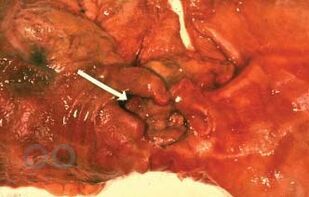

В третьей части учебного пособия «Осложнения язвенной болезни желудка и двенадцатиперстной кишки» отражены вопросы этиологии и патогенеза, классификации, клиники, диагностики, дифференциальной диагностики, консервативного и хирургического лечения язвенной болезни желудка и двенадцатиперстной кишки, осложненных пенетрацией, пилородуоденальным стенозом и малигнизацией.